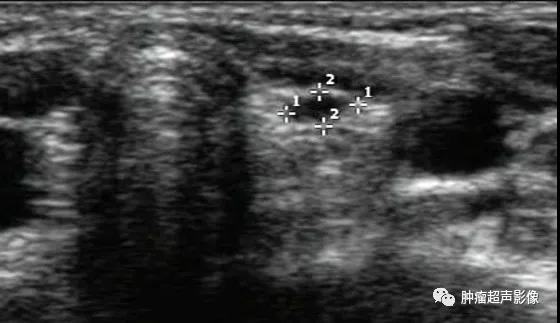

异位甲状腺(迷走甲状腺):正常甲状腺位置未见甲状腺回声,双侧颌下见甲状腺样组织回声,左侧异位甲状腺内见囊肿